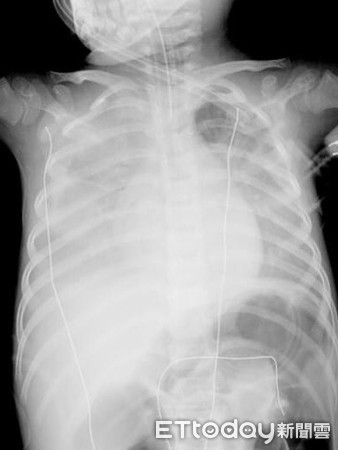

Bác sĩ Ngô nhớ lại rằng, tình hình lúc đó rất nguy cấp, kết quả xét nghiệm ban đầu cho thấy âm tính với bệnh cúm. Tuy nhiên, cậu bé bị tăng bạch cầu và tăng axit chuyển hóa trong máu. Chụp X-quang cho thấy thùy phổi 2 bên có vấn đề. Những dấu hiệu này chứng tỏ cậu bé bị viêm phổi nặng, thậm chí còn có các triệu chứng suy hô hấp và bất tỉnh. Bác sĩ quyết định đặt nội khí quản ngay lập tức.